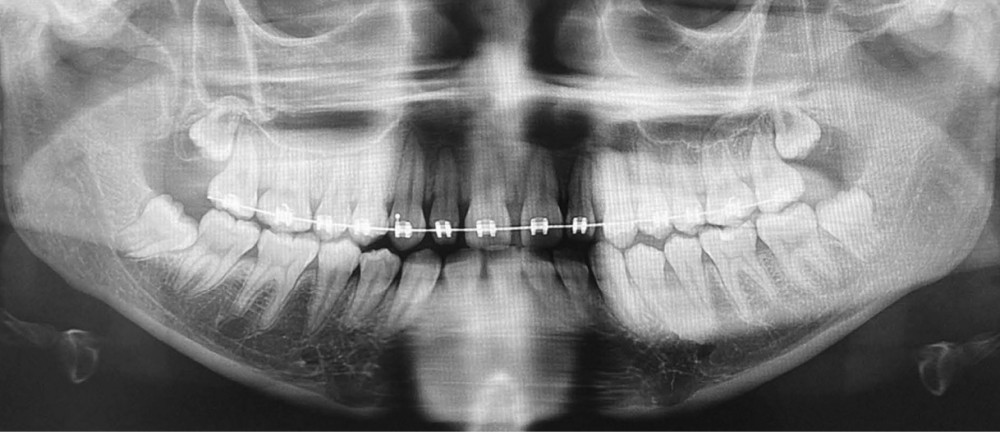

La radiographie panoramique permet de confirmer l’inclusion de la 23, apicale aux dents 21 et 22, ainsi que la présence d’un odontome en apical de la 63. Ces éléments nécessitent la réalisation d’un CBCT.

Le CBCT révèle une position très apicale de la 23. L’apex est fermé.